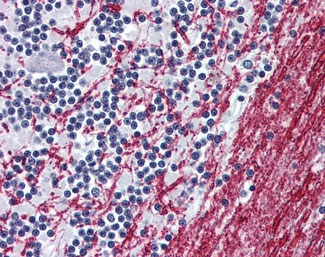

Anti-OPRM1 / Mu Opioid Receptor antibody AMM06915G IHC of human brain, cerebellum. |